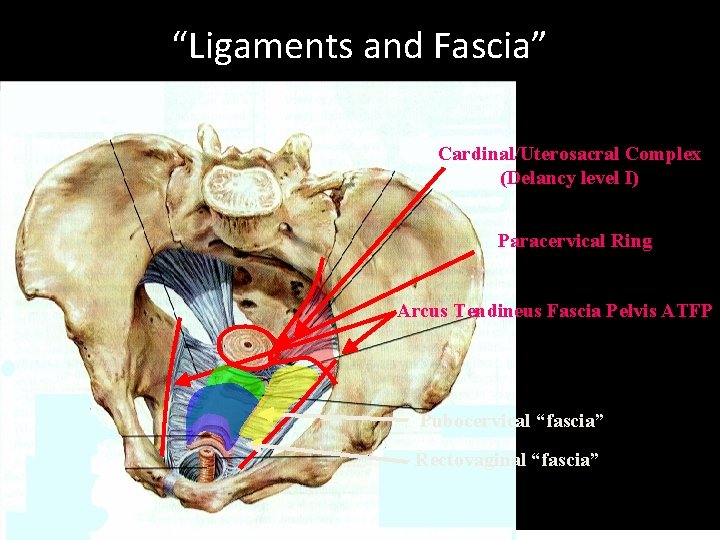

“Ligaments and Fascia” Cardinal/Uterosacral Complex (Delancy level I) Paracervical Ring Arcus Tendineus Fascia Pelvis ATFP Pubocervical “fascia” Rectovaginal “fascia”